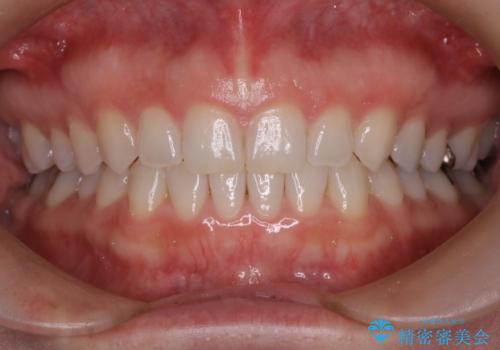

コンプレックスだった前歯のガタガタがここまで綺麗になるなんて!!